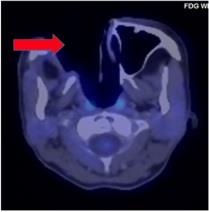

![]() ![]() ![]() |

| Sau 24 chu kỳ, khối u lympo của chị N.A đã tan. |

Các bác sĩ đã quyết định điều trị khối u của chị N.A bằng thuốc ức chế tụ điểm miễn dịch. Chỉ sau vài chu kỳ điều trị, khối u tan hoàn toàn, người bệnh hết đau, dễ chịu hơn mà không có tác dụng phụ nào.

Chị N.A là một trong số ít trường hợp u lympho tế bào T/NK ngoài hạch type mũi trên cả nước điều trị đáp ứng hoàn toàn. Sau 2 năm, với 35 chu kỳ điều trị dùng thuốc miễn dịch và được theo dõi sát sao, hiện chị N.A không có dấu hiệu tái phát - di căn. Trong tương lai, bệnh nhân tiếp tục được điều trị duy trì bằng thuốc miễn dịch này để đảm bảo hiệu quả chữa bệnh.